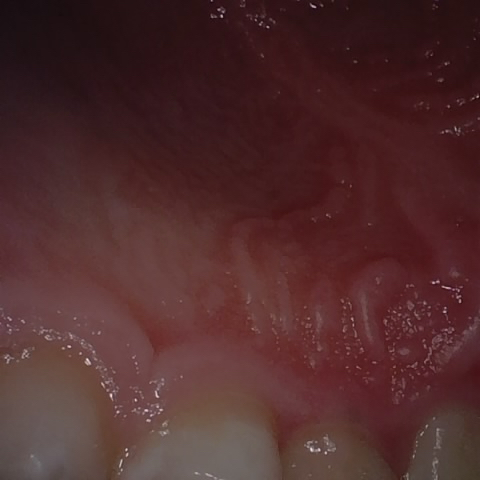

Annotated as "Good"